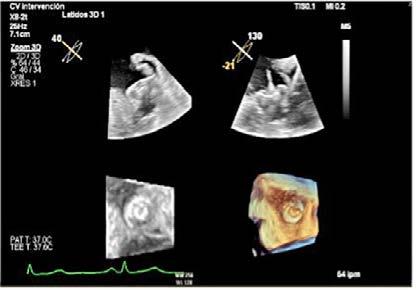

Mujer de 73 años con antecedentes de hipertensión arterial, trombopenia en contexto de lupus eritematoso sistémico, episodio de hipotiroidismo inducido por amiodarona y fibrilación auricular (FA) en estrategia de control de frecuencia cardiaca, anticoagulada con antivitamina K. Como fundamental antecedente cardiológicos destaca una valvulopatía reumática con afectación mitral, que inicialmente se reparó en 1997 mediante abordaje transapical (dejando como secuela aneurisma apical) y se recambió en 2007 por prótesis mecánica. Posteriormente, fue diagnosticada de doble lesión aórtica reumática con estenosis severa e insuficiencia ligera, con fracción de eyección preservada, pero insuficiencia tricuspídea severa e hipertensión pulmonar de predominio poscapilar. Ingresó programada para implante percutáneo de válvula aórtica (TAVI) vía transfemoral, con los principales condicionantes de bloqueo de rama derecha y altura límite de tronco coronario izquierdo (TCI), por lo que se administró clopidogrel 600 mg previamente al procedimiento.

Previo implante de marcapasos temporal yugular derecho se llevó a cabo el procedimiento. Durante la liberación de prótesis mediante inflado del balón, tuvo lugar la embolización supra-anular de la misma, dejando por un lado una insuficiencia aórtica severa y por otro lado ocluyendo parcialmente ambos troncos coronarios. Empleando doble acceso radial se enganchó la prótesis mediante un lazo y se desplazó hacia aorta ascendente, dejando hueco para la colocación de una segunda prótesis en situación correcta y evitando la oclusión de los ostium coronarios y troncos supra-aórticos. En ausencia de bloqueo auriculoventricular se retiró el marcapasos temporal, se evidenció un hematoma yugular derecho y, a través de analítica, se detectó anemización de 2,5 puntos. Mediante angiografía, se descartó enfermedad coronaria y, mediante ecocardiograma transesofágico, se confirmó normoposición de la prótesis, objetivándose al mismo tiempo una disección aórtica.

Se realizó una tomografía computarizada (TC) con contraste de forma emergente, que mostró una disección aórtica iatrogénica tipo A focal de origen en la zona 0 del cayado con extensión al tronco braquiocefálico derecho (1) sin afectar al resto de troncos supra-aórticos, cayado o aorta descendente (Figuras 1 y 2); además del hematoma

Figuras 1 y 2: Prótesis aórtica migrada y disección aórtica focal tipo A, de origen en la curvatura menor del arco aórtico (zona 0) hasta la bifurcación de la arteria braquiocefálica derecha; sin afectación de del resto de troncos supra-aórticos, del resto del cayado aórtico o de la aorta descendente.